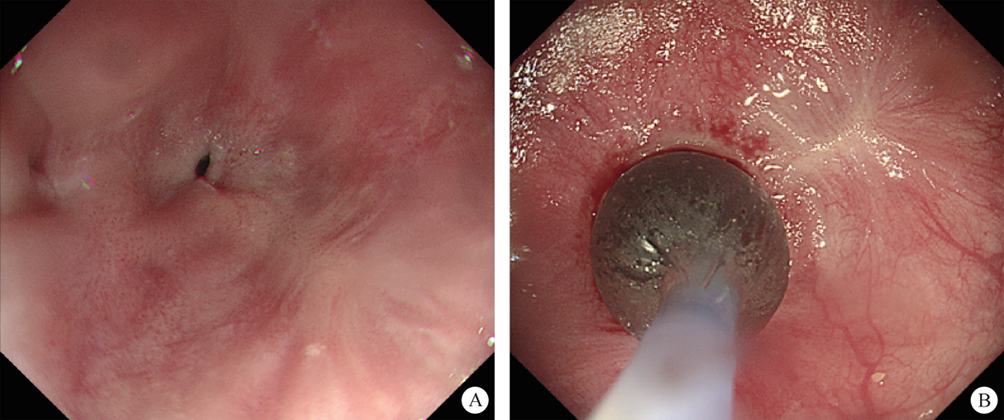

(II) Approach via tunnel channel

This refers to the operation that meets the super minimally invasive requirements in the artificially created space by reaching the surgical site through an artificially established channel in the tissues. For instance, thyroid surgery and breast surgery through subcutaneous channels, mediastinal surgery via a supraclavicular channel, surgery for lumbar disc herniation through the back channel, and a series of operations using the gastrointestinal endoscopic tunnel technique. The following text will take the SMIS through the digestive tunnel technique as an example to present this channel (figure 2.2).

FIG. 2.2 — SMIS through a tunnel channel.

The digestive endoscopic tunnel technique (DETT) is a treatment technology using an endoscope to establish a channel between the mucosal muscle layer and the fixed muscle layer under the digestive mucosa, and leads to the mucosa side, to the muscularis propria side and, through muscularis propria, to the outside of the digestive lumen. DETT isolates the digestive lumen from other lacunae of the human body by preserving the integrity of the mucosal muscle layer or the proper muscle layer, avoiding the entry of gas and of digestive fluids, and maintaining the integrity of the structure of the human body during the treatment. Such therapeutic methods, including POEM, STER, and ESTD, are currently widely used in clinics.